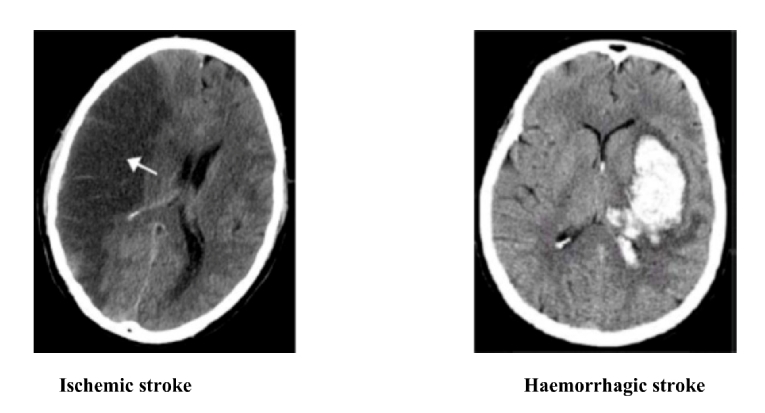

The incidence of ICH and fatal bleeding with OACs increased with age. A delicate balance should be maintained when using OACs to prevent a TE event without inducing major or fatal bleeding (Figure 1).

Figure 1. Very old patients with atrial fibrillation have increased risk of ischaemic stroke and of haemorrhagic stroke; therefore, a good knowledge and careful handling of oral anticoagulants are needed.